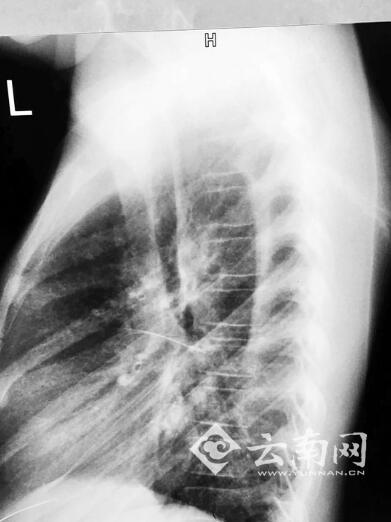

经过急救科详细诊断,可以确诊钢针从胸腔剑突下向上斜刺入小甜心房。更为严重的是钢针已经断成两截,针头部分直刺入右心房,针尾一截留在皮肤与胸膜间。专家分析后认为,是心脏巨大的收缩和扩张力量,硬生生将钢针折断。

经过专家会诊后,决定先由胸外科将胸膜里的针尾取出,再由心外科组织手术将刺入右心房的针头取出。

据心外科主任庞中一介绍,当时情况非常危急,因为针头刺破部分心血管,小甜心房内已经积压大量淤血,随时可能因“心房填塞”而猝死。